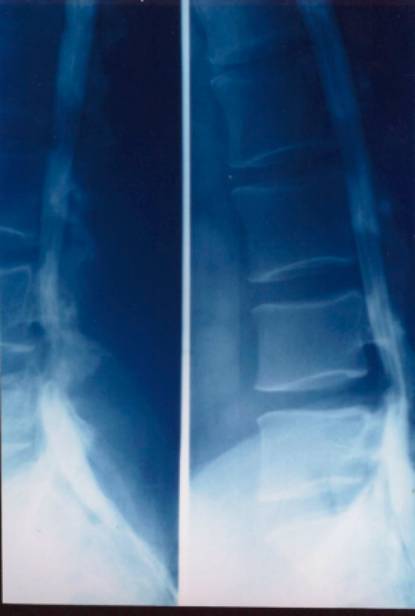

1、X线检查:脊柱曲度的改变;椎间隙变窄;椎体缘骨赘;关节突关节退变肥大;椎体滑脱;神经根管狭窄伴有椎间关节半脱位。

上椎体下缘的后延线不是穿越下椎体上关节突的端,而是穿过中间;正位片显示:正常的“S”弧线消失

X线平片:可明确显示椎管矢状径较正常为狭小,其绝对值于15mm,甚至在12mm以下,个别病例不足10mm。